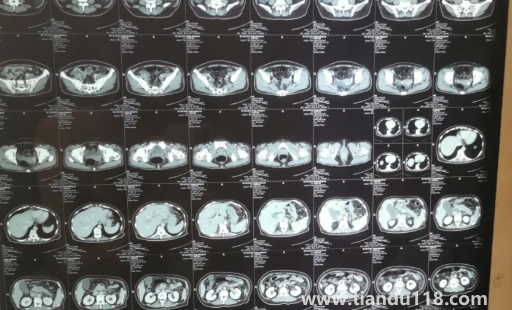

胰腺不舒服早期大便會變化嗎

胰腺患者早期大便不會有明顯影響,也有少數(shù)患者早期大便有明顯變化,如大便不暢及便秘、大便時(shí)疼痛等不適。 有的患者可能數(shù)日無大便,有的患者可能出現(xiàn)腹痛或發(fā)熱等癥狀,大便變化也沒有太嚴(yán)重。 患者應(yīng)及時(shí)就診,避免耽誤時(shí)間過長加重病情,并在醫(yī)生指導(dǎo)下服藥。 平時(shí)需要注意日常飲食和生活習(xí)慣,多注意休息,避免過度勞累。